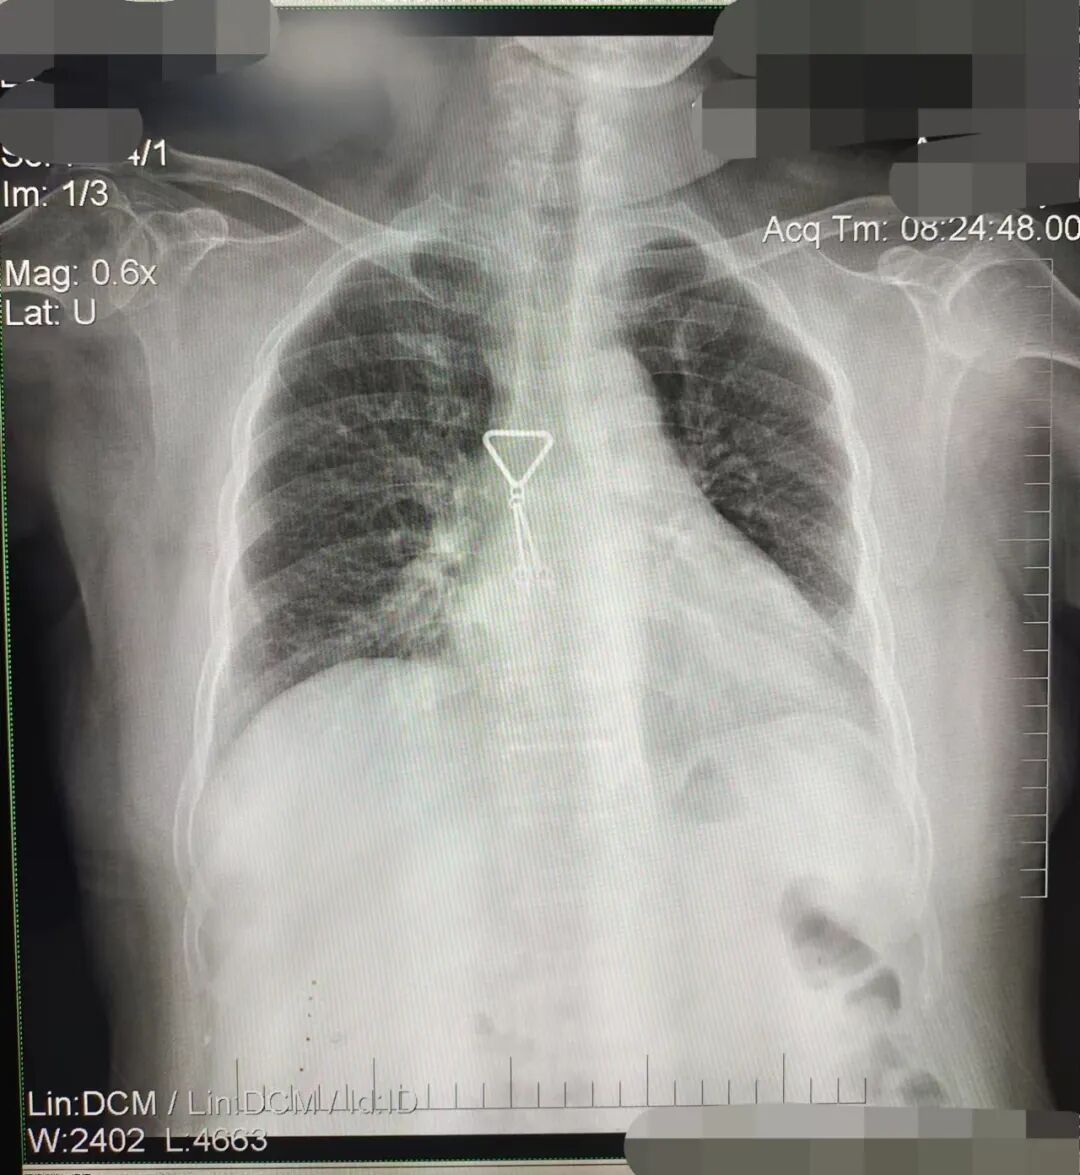

DR胶片为什么分尺寸借DR成像原理详解胸部正位摄片技术参数_https://www.jmylbn.com_新闻资讯_第10张

缺陷:左肩胛骨部分与左肺野重叠。

解决:使患者左肩旋前紧贴成像件重新曝光。